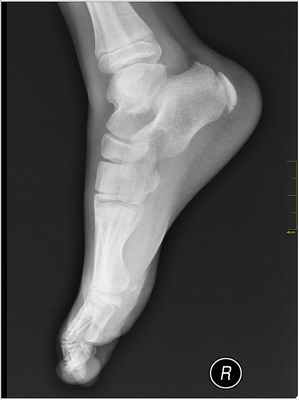

- Рентгенография: в большинстве случаев рентгеновские снимки оказываются бесполезными, поскольку очень часто у детей апофиз пяточной кости фрагментирован и плотен. Однако с помощью рентгена можно исключить другие травмы.

Рентгенологически определяется уплотнение, склерозирование и фрагментация апофиза с расширением щели между апофизом и костью. Разобраться, где нормальный центр вторичного окостенения, а где изменения в нем, характерные для болезни Севера, не так просто. Трудности рентгенологической диагностики связаны с тем, что в норме апофиз имеет до 4 ядер окостенения, одно из них (чаще среднее) уплотнено, а смежные поверхности пяточной кости и апофиза «зазубрены». Видимо, сам Sever испытывал трудности в диагностике «своего» заболевания, так как писал о том, что вторичный центр оссификации у детей нередко становится более склеротичным и даже фрагментированным без прямой связи с клиникой заболевания.

В основе диагноза лежит динамическое рентгенологическое исследование, при котором на ранних этапах выявляется пятнистая структура уплотненного ядра окостенения, сменяющаяся фрагментацией апофиза и затем перестройкой с формированием нового губчатого вещества.